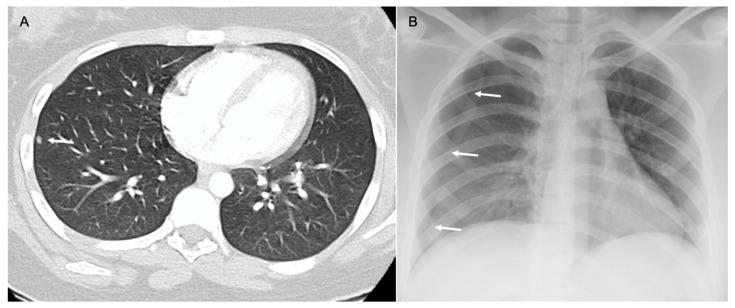

Osteosarcoma, a primary bone malignancy in children and adolescents, frequently metastasizes to the lungs, contributing significantly to morbidity and mortality. At diagnosis, 15-20% of patients present with detectable lung metastases. Chest computed tomography (CT) is vital for the early detection and monitoring of these metastases. Lung involvement typically presents as multiple nodules of varying sizes and can include atypical features such as cavitation, cystic lesions, ground-glass halos, intravascular tumor thrombi, and endobronchial disease. Pleural metastasis often occurs alongside pulmonary disease, and complications like spontaneous pneumothorax may arise. Additional findings may include thoracic lymphadenopathy, cardiac tumor thrombus, and chest wall deposits. Familiarity with these imaging patterns is essential for radiologists to ensure timely diagnosis and effective management. This review highlights the critical role of chest CT in detecting and characterizing osteosarcoma metastasis.

骨肉瘤是儿童和青少年常见的原发性骨恶性肿瘤,常转移至肺部,对发病率和死亡率有显著影响。在诊断时,15%至20%的患者出现可检测到的肺转移。胸部计算机断层扫描(CT)对于这些转移灶的早期检测和监测至关重要。肺部受累通常表现为大小不一的多个结节,可包括一些非典型特征,如空洞形成、囊性病变、磨玻璃晕、血管内肿瘤血栓和支气管内病变。胸膜转移常与肺部疾病同时发生,可能出现自发性气胸等并发症。其他表现可能包括胸内淋巴结肿大、心脏肿瘤血栓和胸壁转移灶。放射科医生熟悉这些影像学表现对于确保及时诊断和有效治疗至关重要。本综述强调了胸部CT在检测和鉴别骨肉瘤转移方面的关键作用。